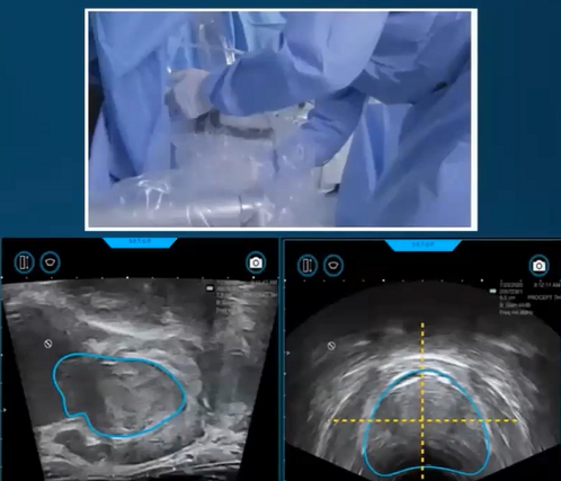

Aquabeam utilizza un getto d’acqua ad alta velocità, guidato da un sistema di intelligenza artificiale e imaging in tempo reale. Questo consente al chirurgo di pianificare e realizzare l’intervento con una precisione mai vista prima, adattandolo alle specifiche esigenze del paziente.